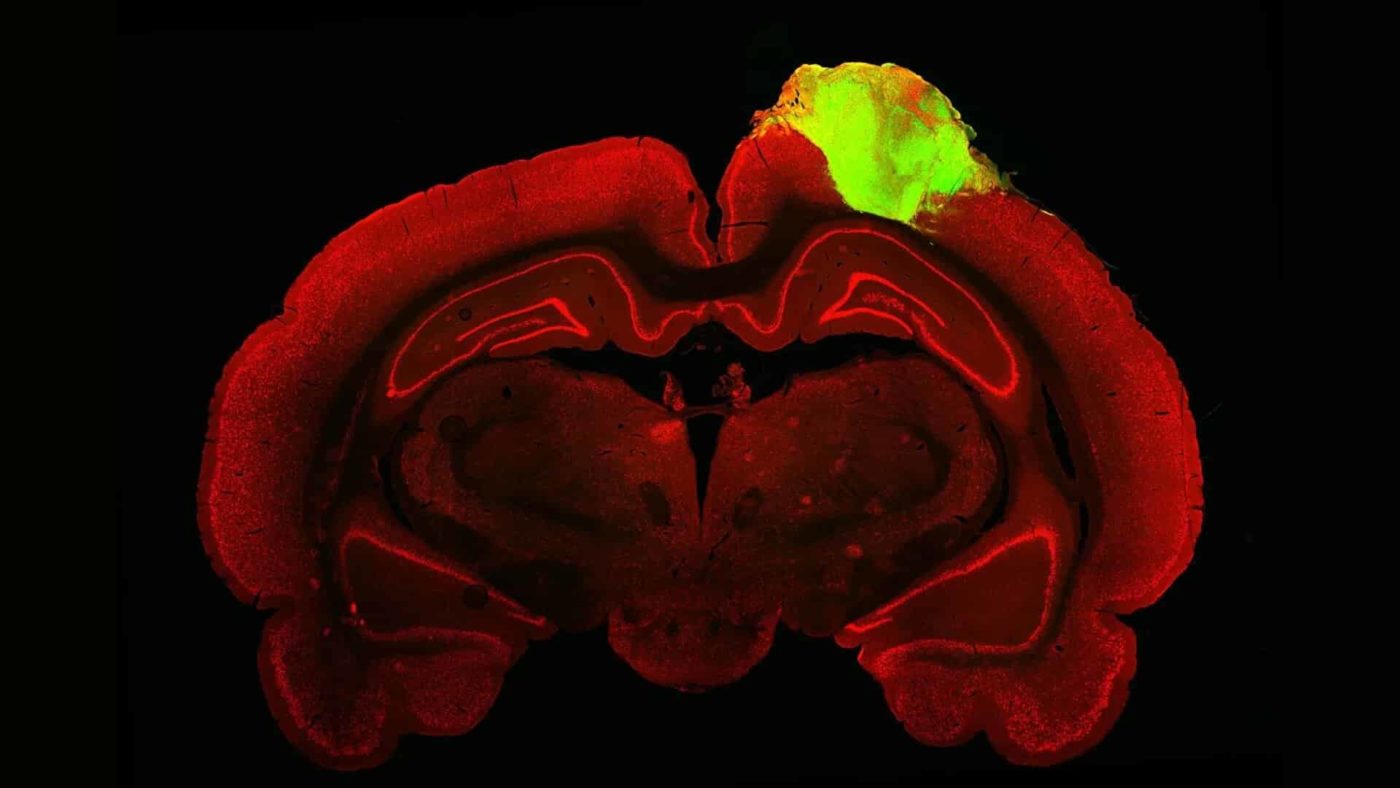

Исследователи восстановили повреждения мозга у крыс путем имплантации органоидов человеческого мозга

В области медицинских исследований последние пять лет наблюдалось стремление к «межвидовой» трансплантации органов. Например, в прошлом году исследователям впервые удалось имплантировать скопления человеческих нейронов в мозг здоровых крыс. В продолжение…